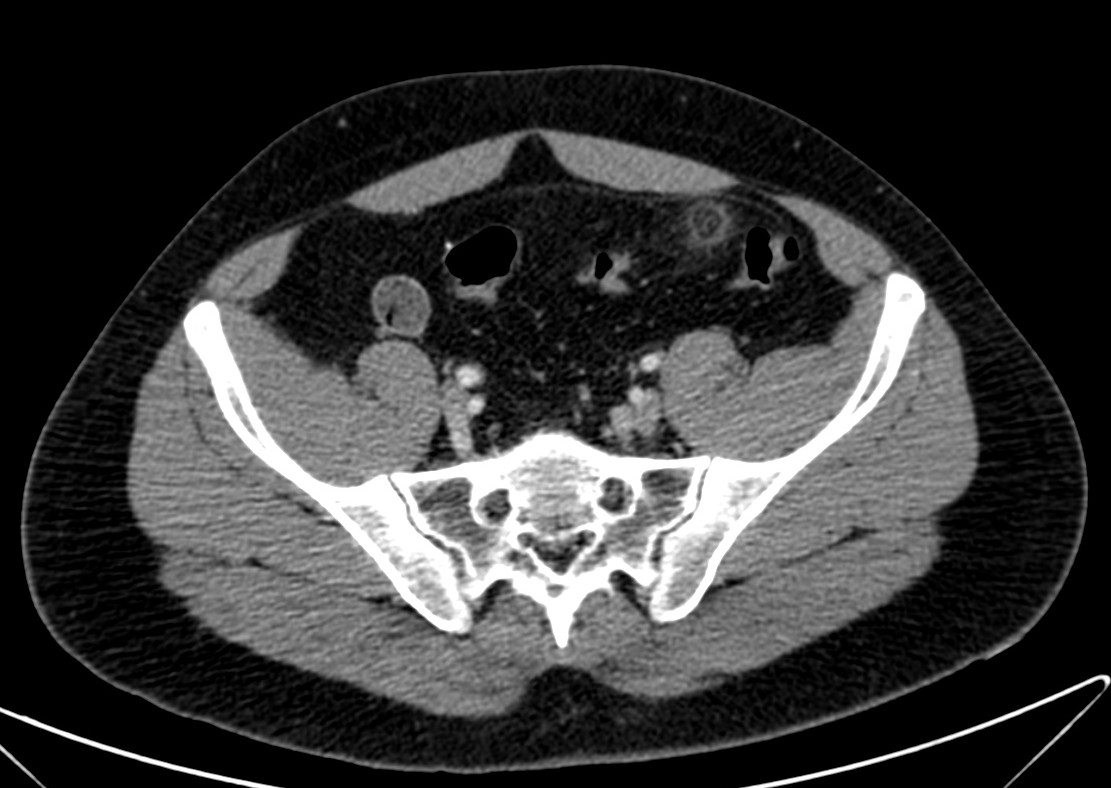

Se sospecha diverticulitis, se realiza TAC de abdomen:

Al igual que el caso anterior, nos encontramos nuevamente ante una apendagitis. Esta vez la sospecha era por diverticulitis, la anterior creíamos enfrentarnos a una apendicitis probablemente.

TAC: Imagen oval con aumento de la atenuación central, inferior a 5 cm de diámetro, contigüa al colon, con afectación de la grasa periférica. El aumento de la atenuación central es un signo de trombosis venosa muy útil para el diagnóstico, pero su ausencia no excluye en diagnóstico de apendagitis. Otros hallazgos, como aumento de la pared colónica o formación de abscesos son raros. Aunque los síntomas remiten en dos semanas, los cambios en la TAC pueden prolongarse más tiempo (pueden mantenerse, disminuir o quedar una atenuación residual), aunque en 6 mese suele haber remitido completamente. En Ecografía suele observarse en el área de máxima sensibilidad al dolor, una masa hiperecogénica, inferior a 5 cm, no compresible, adyacente al colon y sin señal Doppler.